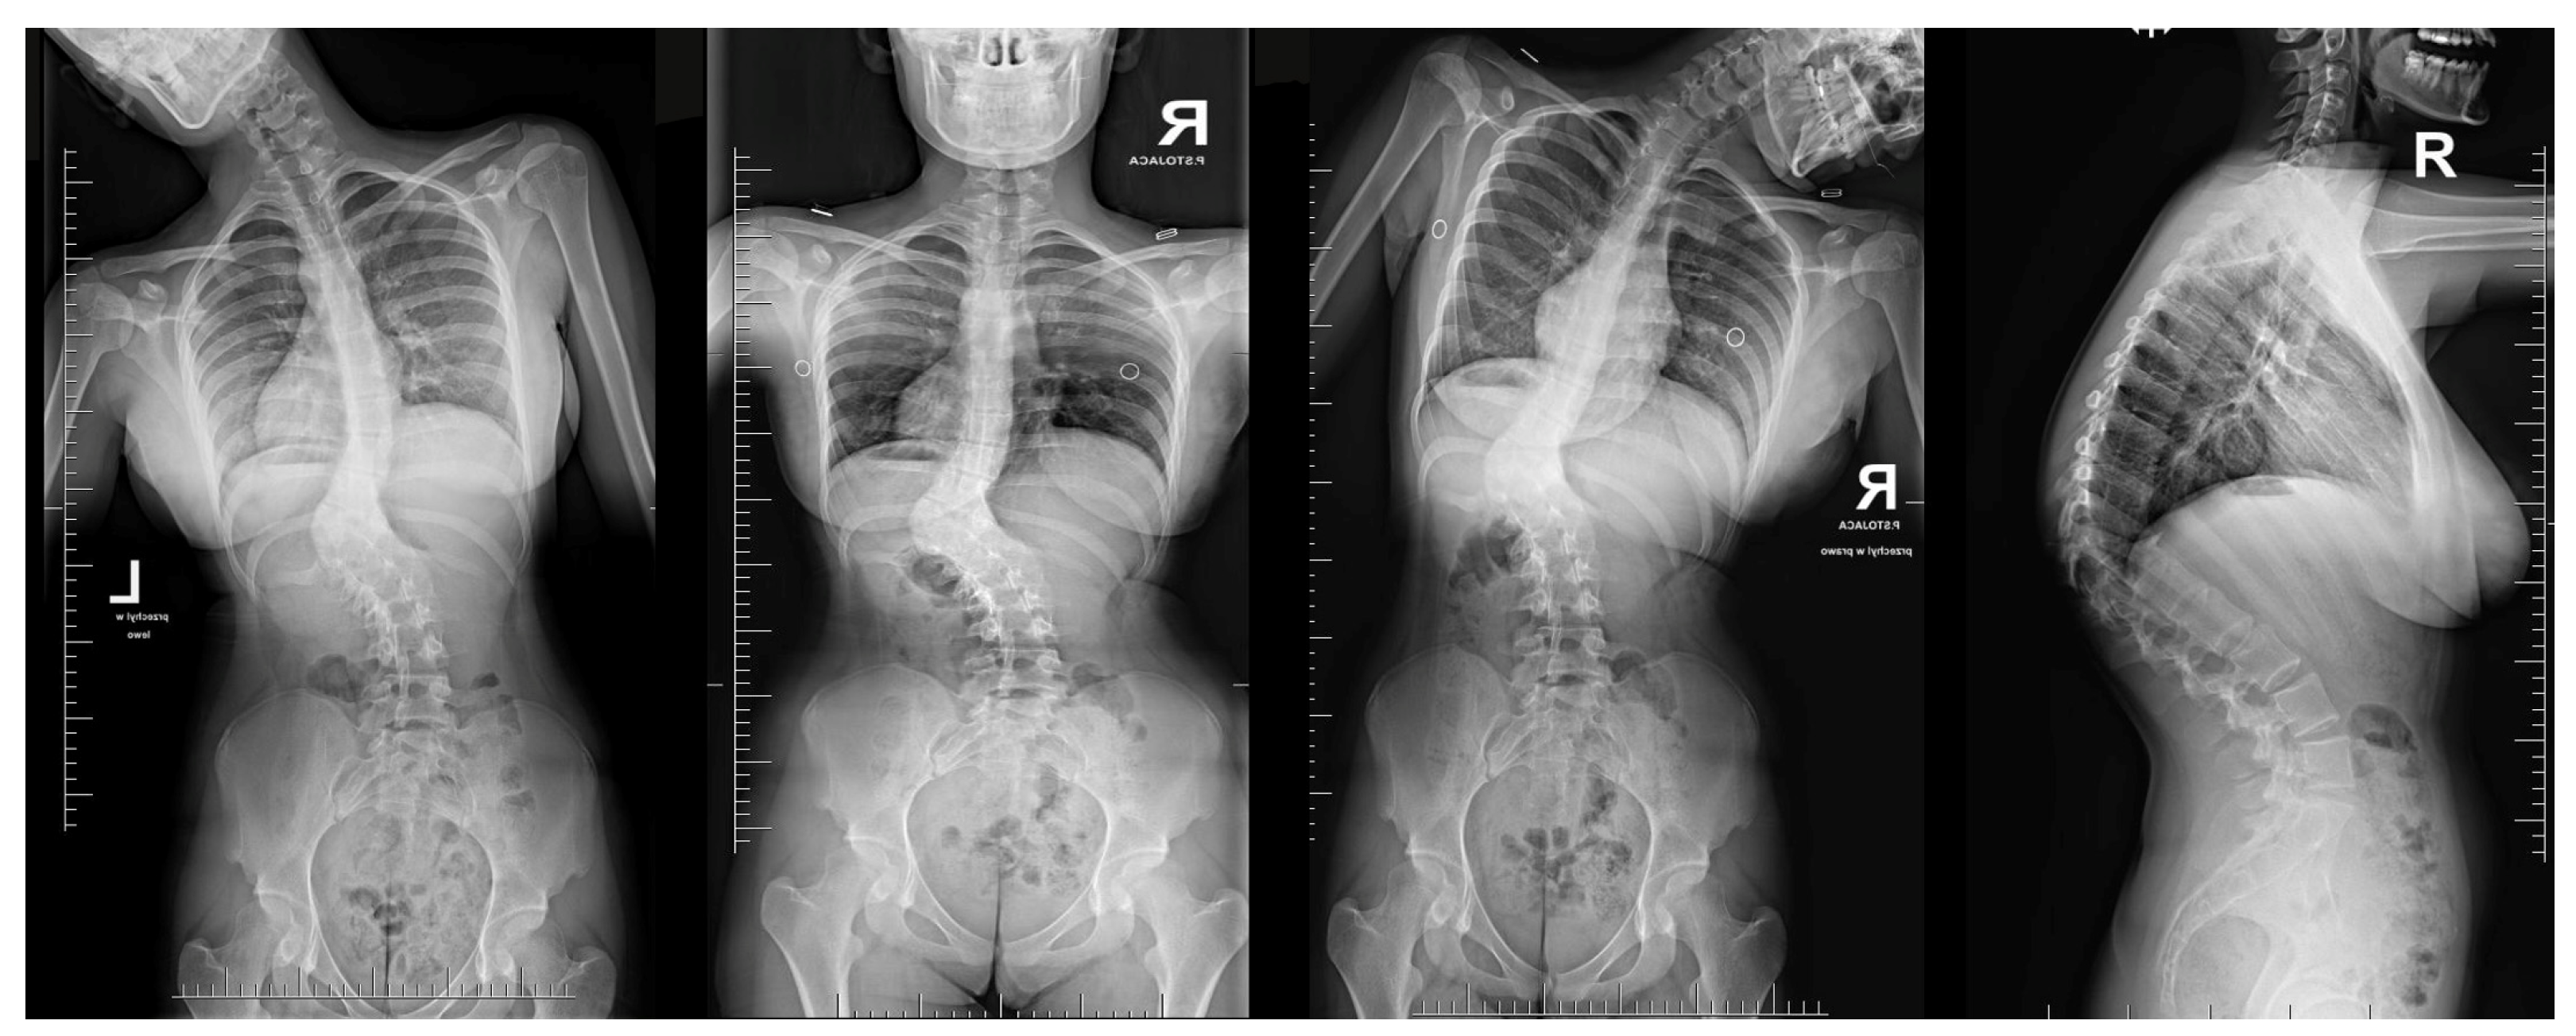

A 16-year-old female patient came to our clinic because of a progressive spinal deformity. She was diagnosed with a congenital spinal deformity at 9 years of age. Conservative measures such as bracing were used but were unsuccessful, and her curve progressed over time. Additionally, at 9 years of age, an MRI confirmed the absence of intraspinal pathology and congenital thoracolumbar kyphoscoliosis. During the examination in our clinic, she presented with a progressive rib hump and shoulder asymmetry in the Adams forward bend test. She also had a severe thoracolumbar hump, underlying back discomfort and pain when sitting and at night, and a Risser score of 3/4 (Figure 1).

Neurological examinations showed full strength (5/5) in all major muscle groups of BUE/BLE, sensation intact throughout, normal reflexes (including abdominal), and pain on palpation in the thoracic spine above and below the gibbous. The neuro-imaging findings indicated a Cobb angle of 63° in the main thoracolumbar curve. The flexibility of the curve was measured at 63° when bending, decreasing to 48°. Additionally, there was a thoracic kyphosis of 4° between T2 and T5 and 32° between T5 and T12, with a severe focal thoracic kyphosis of 108° (Figure 2).

Figure 2. Standard standing AP and lateral X-rays and side-bending films of the 16-year-old female before surgical treatment. These X-rays showed severe and stiff congenital kyphosis.